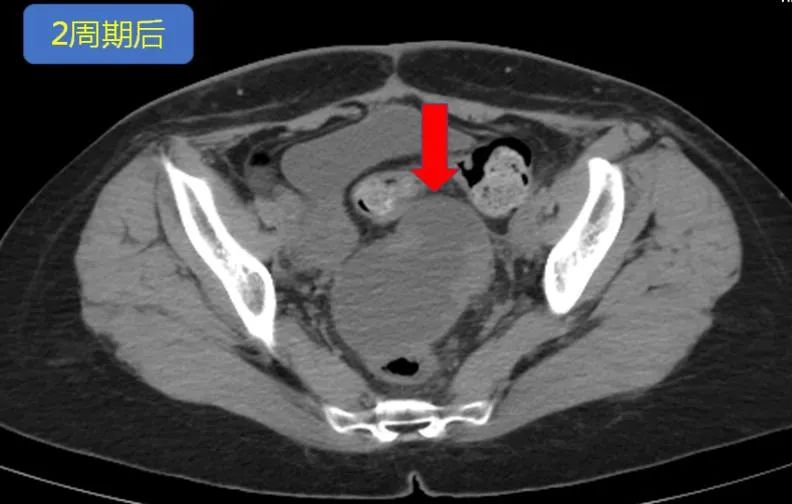

△PD-1抗体治疗两周期后

肿块持续增大!肠梗阻再次手术。

应用PD-1抗体1个多月后,2018年8月,复查发现,张女士盆腔及腹膜后肿块持续增大增多(图2所示)。

雪上加霜的是,张女士因肿块增大,堵塞肠腔,导致了肠梗阻,肚子胀痛,吃东西吐出来,无法放屁、排便,痛苦不堪。普外科袁龙主任医师为其进行了“横结肠造瘘术”。